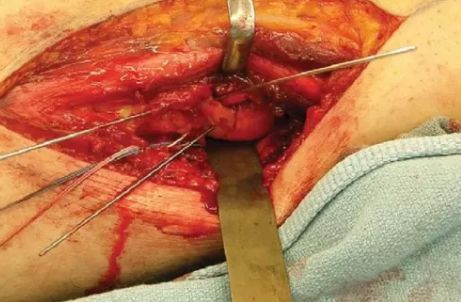

操作:自股骨外上髁至腓骨颈做一纵向切口,首先在腓骨颈远侧显露腓总神经,并向近侧游离,切开股二头肌肌腱(前)和腓总神经之间的深筋膜,股二头肌牵向外侧,腓总神经牵向内侧,显露后外侧关节囊,自远侧半月板附着部位向近侧纵向切开关节囊,在半月板位置的关节囊留置缝线,用以牵开关节囊显露股骨远端。

患者仰卧位,自股骨外上髁至腓骨颈做一纵向切口。

切开股二头肌肌腱(前)和腓总神经之间的深筋膜。

显露腓总神经,股二头肌牵向外侧,腓总神经牵向内侧。

复位和临时固定。